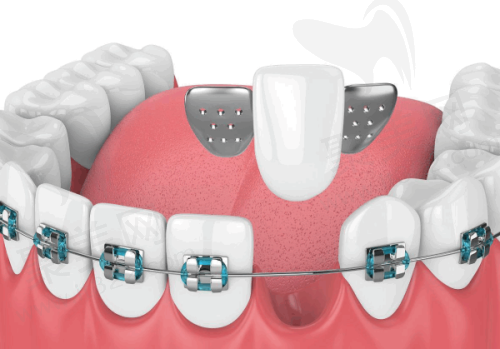

近年来,医院在口腔数字化临床应用等重点领域实现关键技术突破,开展的新技术如基于数字化导板的复杂阻生牙、多生牙拔除、牙颌面畸形综合矫治技术、儿童舒适化口腔治疗等,有效填补省内乃至国内外空白。就拿基于数字化导板的复杂阻生牙、多生牙拔除来说,以前拔除这些牙齿可能就像在黑暗中摸索,而现在有了数字化导板,就像是有了一个精细的地图,医生可以更加正确地进行操作,大大提高了手术的成功几率和安心性。